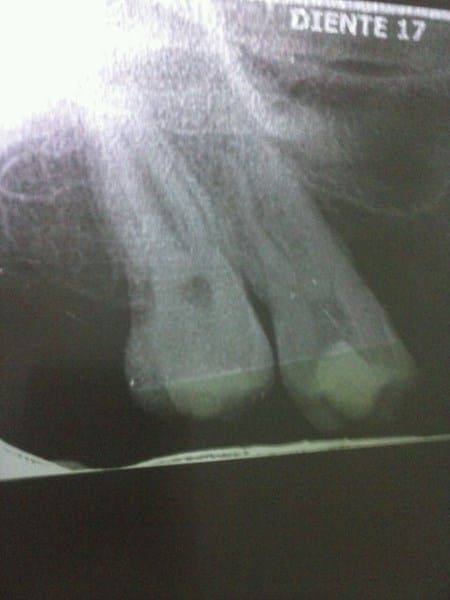

Tengo 24 años hace poco fui a donde una odontologa, por que dolía una de las muelas superiores la 17 ella acabo de hacerme limpieza pero me dejo abierta la muela y me puso algodón por que me debo hacer una radiologia, m, e formulo Azinobin, pero como en la drogeria no habia me dieron una parecida llamada Azitromina, el caso es que me dule muchoo no pudo dejar de hacer buches con solo agua